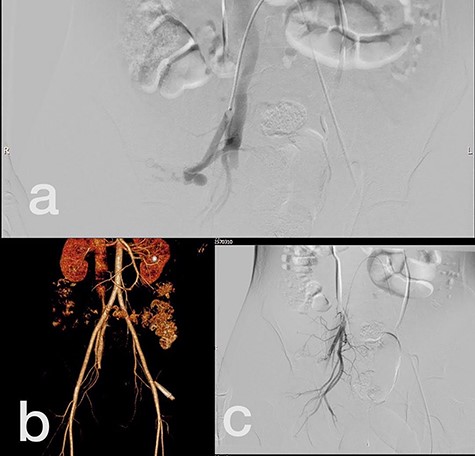

Sites of injury included 6 Posterior Tibialis arteries (27.2%) (Fig. 1), 2 deep femoral arteries (9.09%), 2 Superficial femoral arteries (9.09%) and 2 maxillary arteries (9.09%). We had only one injured artery (4.54%) in each of the following sites: internal pudendal a., Axillary a. (Fig. 2), Proneal a., Lumbar a., External carotid a., Anterior Tibialis a., common iliac a. (Fig. 3), temporal a., Thoracic aorta and Internal iliac artery (Fig. 4).

(a) Internal iliac artery before intervention, (b and c) after coil embolization.